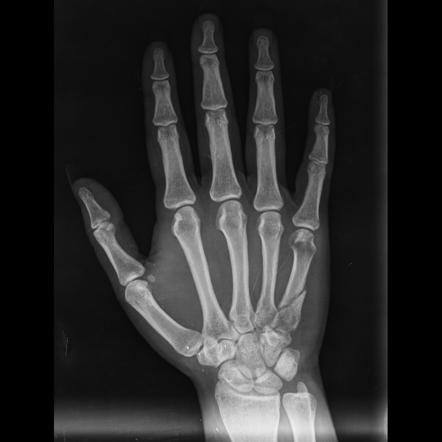

Переломы пястных костей, длинных костей кисти, соединяющих пальцы с запястьем, являются распространенными травмами, часто вызванными падениями, занятиями спортом или прямой травмой.В последние годы значительный прогресс в области медицинских технологий привел к разработке пястных стопорных пластин, что произвело революцию в лечении переломов кисти.Эти инновационные имплантаты доказали свою эффективность.

Переломы пястных костей могут различаться по тяжести и локализации, поражая разные части руки.Они обычно подразделяются на несколько типов, в том числе:

Пястные стопорные пластины представляют собой крупный прорыв в лечении переломов кистей рук.Эти пластины специально разработаны для обеспечения стабильной фиксации и поддержки во время процесса заживления.